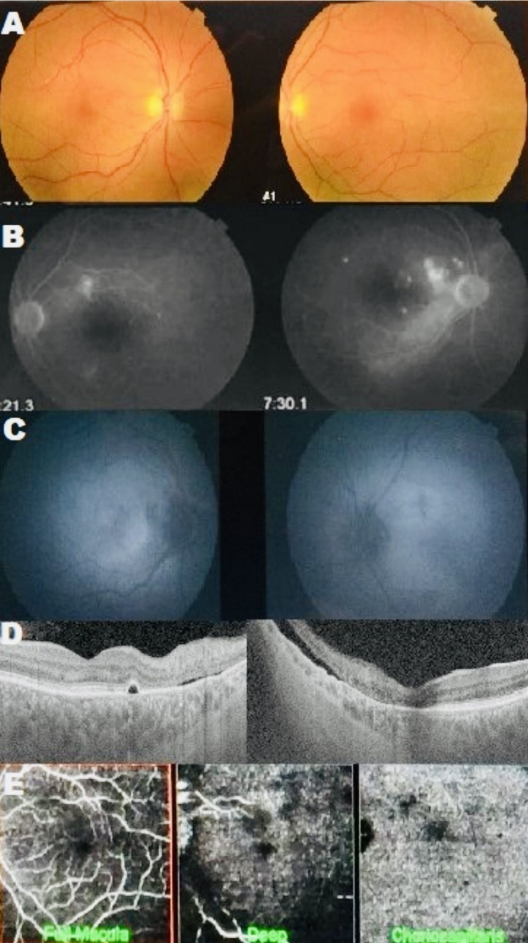

Indocyanine green angiography was not performed. Ipilimumab was discontinued, but the patient declined high-dose systemic corticosteroid therapy. Three months later, visual acuity in the OD had reduced to 0.1, and in the OS to hand movements. Studies showed persistent SRDs (Figure 2A, B [Fig. 2]) and choroidal changes with areas of hypo- and hyperautofluorescence (Figure 2C [Fig. 2]) on autofluorescence, and persistents SRDs (Figure 2D [Fig. 2]) and abnormal choroidal vessels on angiographic OCT (Figure 2E [Fig. 2]).

Figure 2: A: Fundus photographs showing serous retinal detachment (SRD) three months after ipilimumab discontinuation. B: Angiograms showing multiple leakage areas associated with increased background fluorescence. C: Autofluorescence images showing hypoautofluorescent areas with hyperautofluorescent zones corresponding to the SRD. D: OCT revealing multiple RPE detachments associated with SRD. E: Angio-OCT showing dark areas corresponding to SRD with abnormal and telangiectatic choroidal vessels